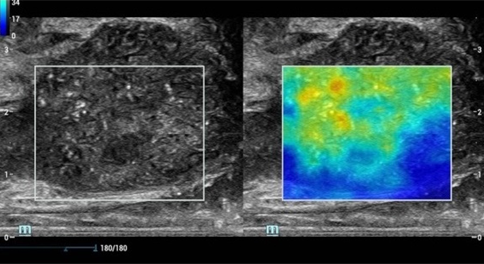

Imagerie ultrasonore par ûˋmission d'ondes planes alimentûˋe par la technologie ZST+, le HiFR CEUS permet une capture CEUS ultra rapide pour la visualisation de la structure vasculaire et des caractûˋristiques de perfusion en phase artûˋrielle, fonctionnant comme un outil complûˋmentaire de l'UWN+

Cas d'utilisation du HiFR CEUS?: HNF du foie

*Il n'est pas recommandûˋ d'appliquer le HiFR CEUS dans la phase de retardement ou dans une rûˋgion û 10?cm de profondeur